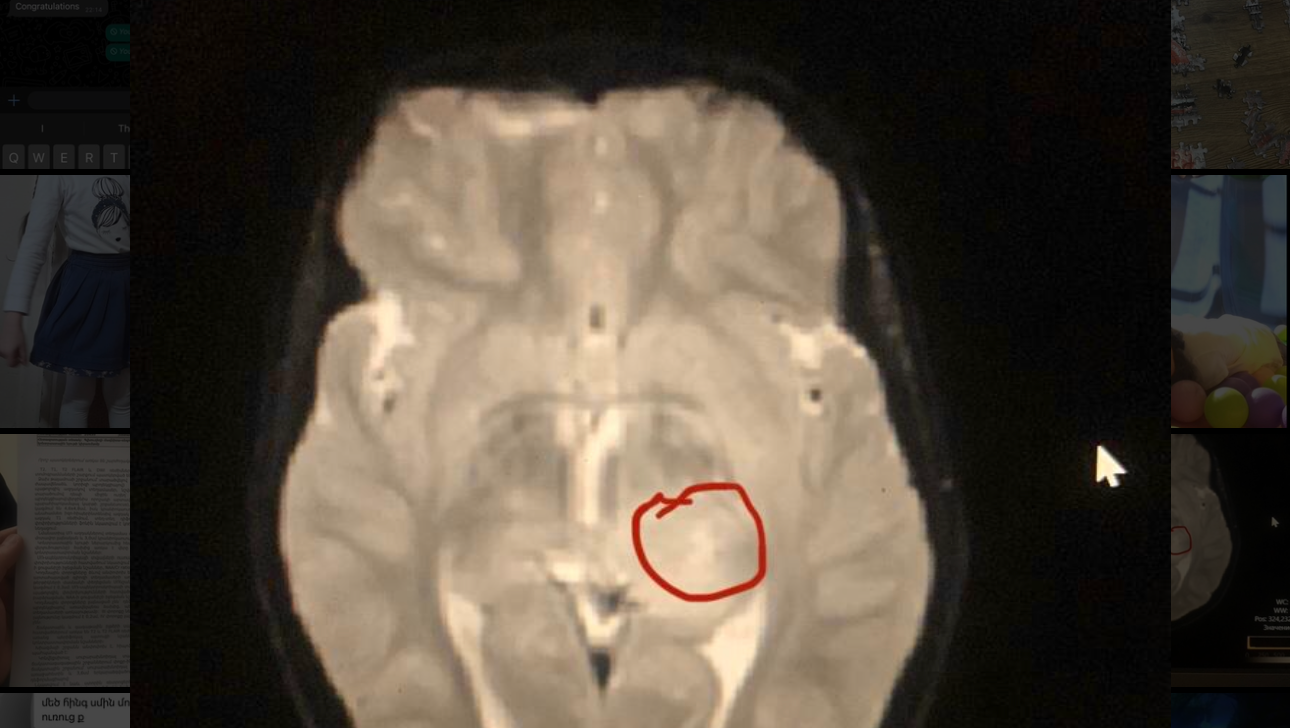

Hi My name is Julieta and I am fundraising for one of my relatives. Her daughter has brain cancer at a critical situation. She is currently located in Armenia. While doctors in Armenia gave no hopes for survival. The mother sent all the paperworks to Germany doctors. In Germany they gave hopes that the child might survive going through Chemotherapy.

Surgery is not an option for us because it’s located in the middle of her brain. ((((